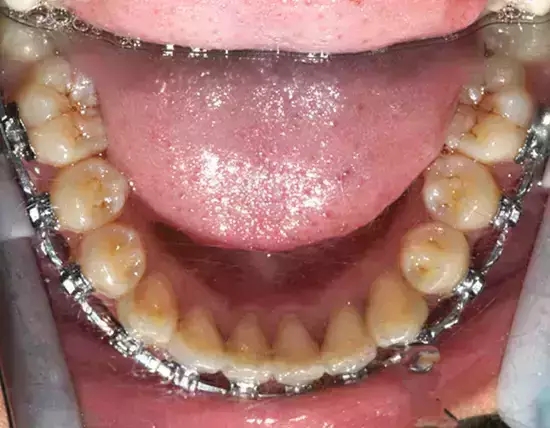

Damon 病例分享:安氏 II 類二分類露齦笑的矯治(董一磊)